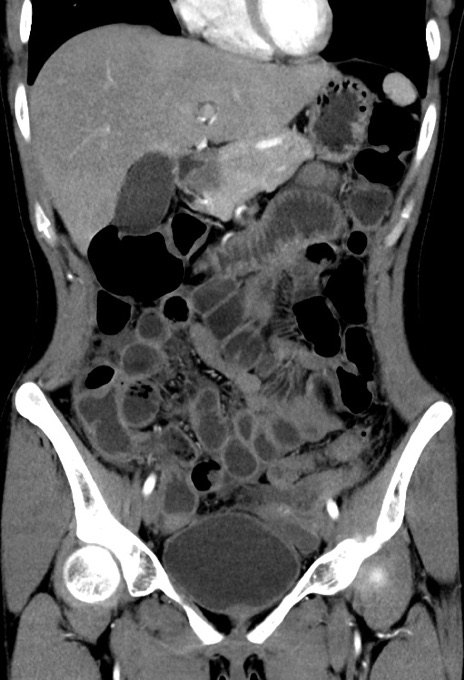

横断像

【症例】20歳代女性

【主訴】嘔吐、下腹部痛

【現病歴】昨日夕食後に嘔吐し下腹部痛が出現。本日になっても嘔吐持続し改善しないため来院。

【身体所見】意識清明、BT 37.2℃、BP 108/67mmHg、腹部:平坦、やや硬、下腹部正中から右にかけて圧痛あり、反跳痛軽度あり、tapping pain(+)。

【データ】WBC 13600、CRP 14.94